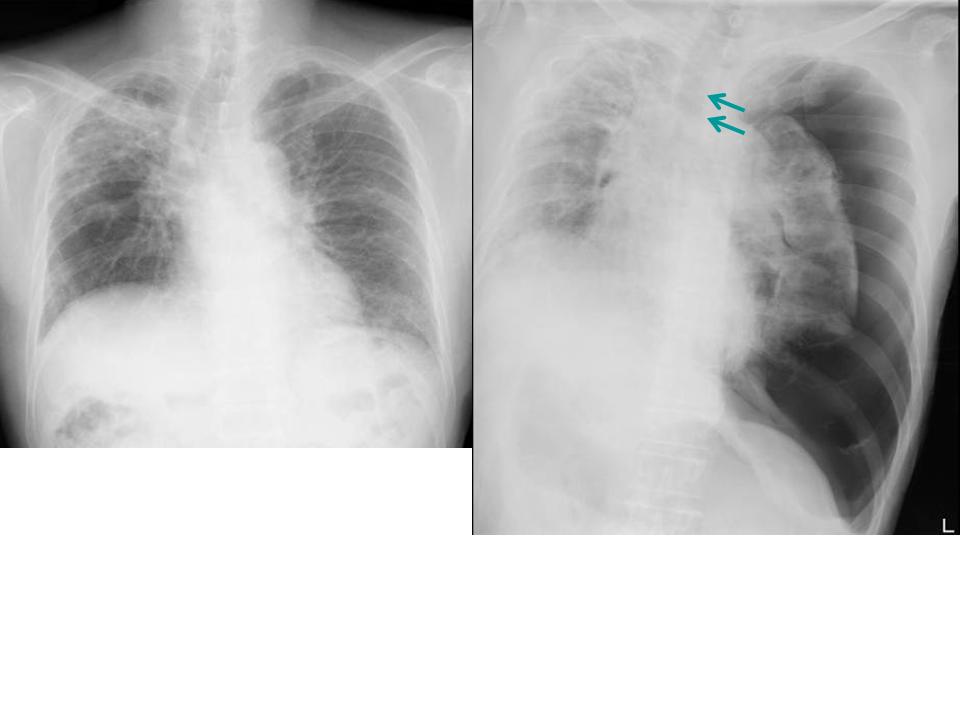

Aシルエット・サインを使う

陰影があったときに、果たしてその陰影はどこにあるのか。

上、中、下肺野のどこにあるかとともに、シルエット・サインをうまく使うことでどのセグメント(

1〜10に分かれている、例のやつ)を絞り込むことができます。

B正面像で見えるリンパ節

傍気管線、A-P window、気管分岐部は必ずチェックしましょう。

C縦隔や横隔膜の動きを見る

これらの動きから、肺容量の増減がわかります。